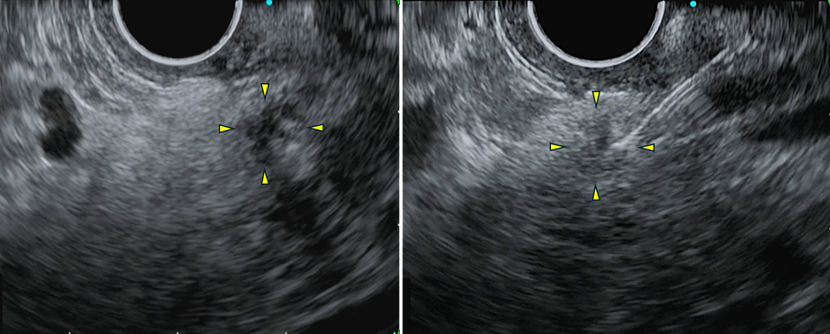

診断が得られなかったため、続いてEUSを行いました。主膵管途絶部に淡い低エコー領域を認めたため(左図)、EUS-FNAを行いました(右図)。その結果、腺癌と診断されました。画像所見から膵上皮内癌(carcinoma in situ)の可能性が高いと考えられたため、術前化学療法は行わず、膵頭十二指腸切除術を施行しました。手術後の病理診断では、膵上皮内癌(Stage 0)と診断されました。

EUS

左:膵管狭窄部の周囲に淡い低エコー領域を認めます。

右:慎重にこの低エコー領域を穿刺しました。